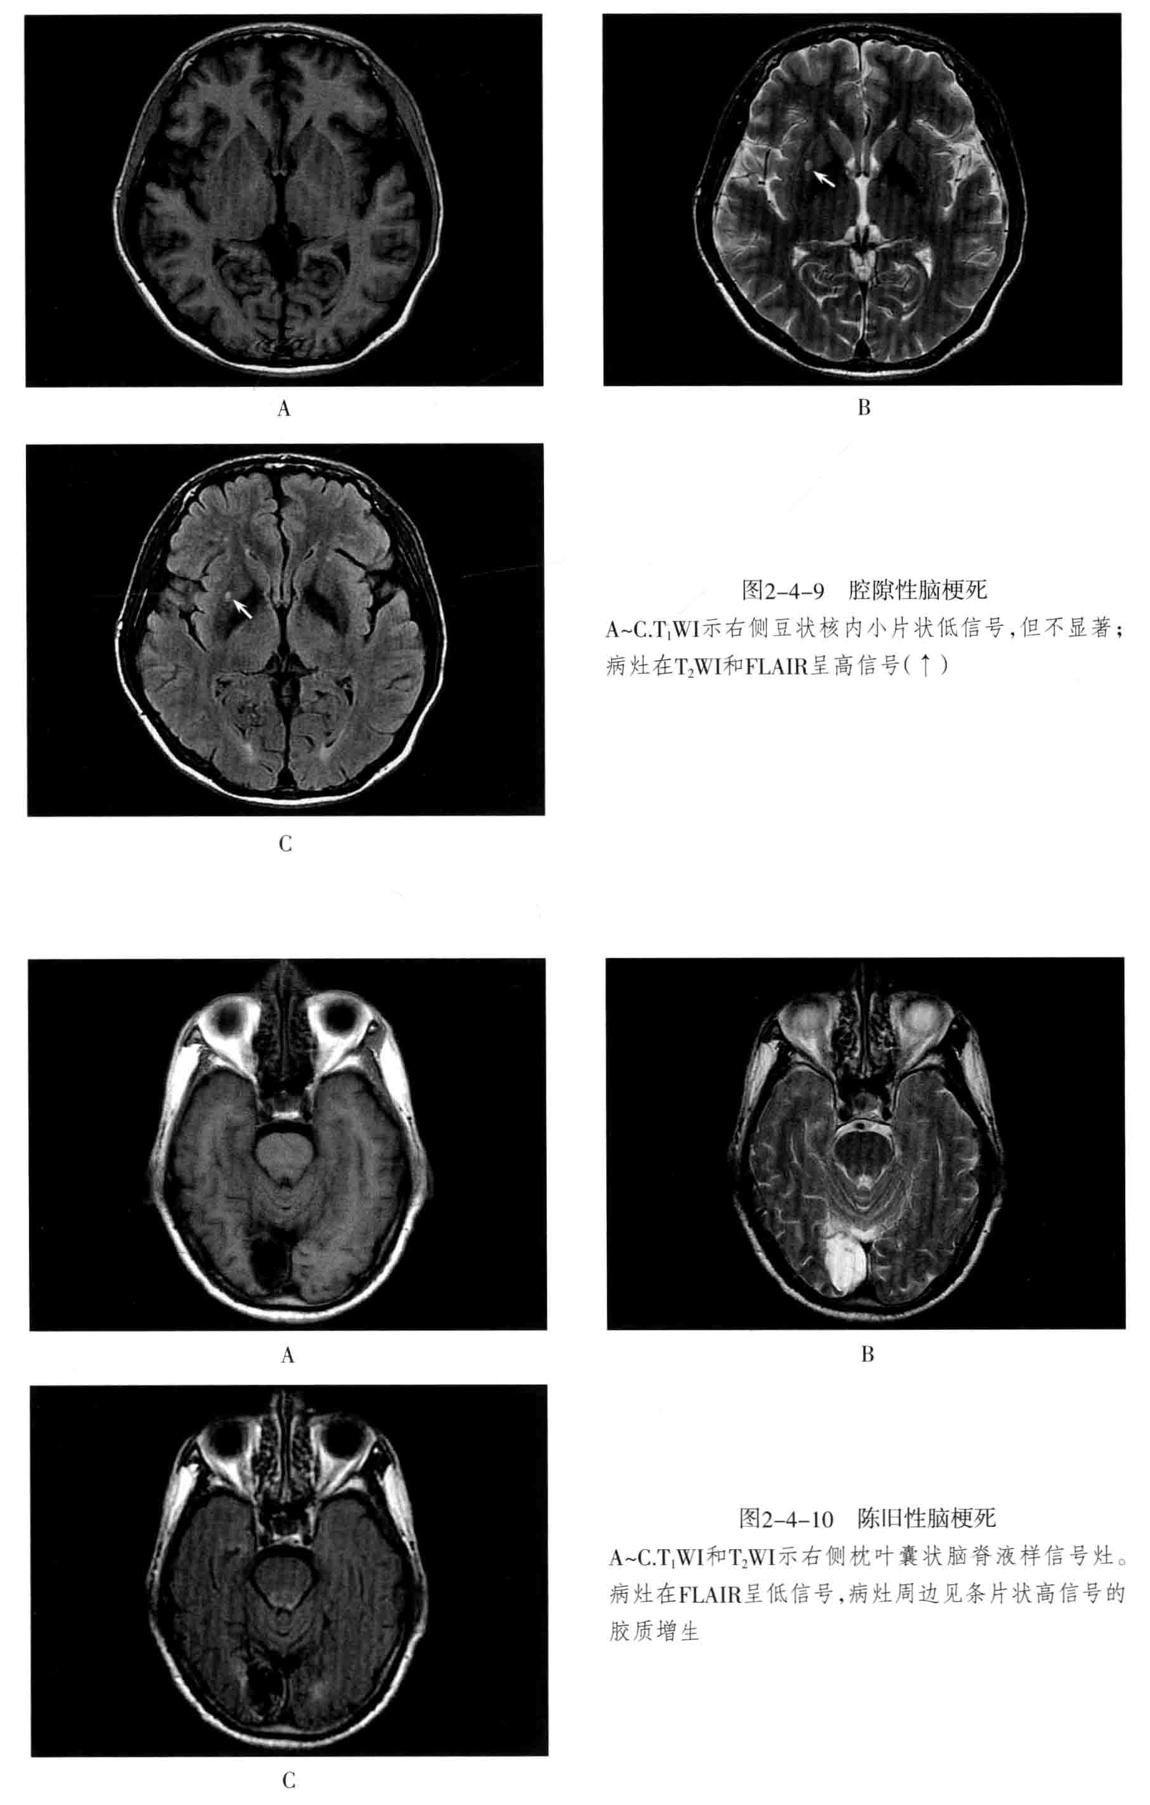

八、脑梗死:是一种缺血性脑血管疾病,常见有动脉闭塞性梗死和腔隙性脑梗死。主要病因为脑的大或中等管径的动脉发生粥样硬化,继发血栓形成,导致管腔狭窄、闭塞。以大脑中动脉闭塞最常见。脑梗死发生4-6小时脑组织发生缺血与水肿,继而脑组织出现坏死。1-2周后脑组织水肿逐渐减轻,坏死脑组织液化,梗死区出现吞噬细胞浸润,清除坏死组织,同时有胶质细胞增生和肉芽组织形成,8-10周后形成含液体的囊腔即软化灶。少数缺血性脑梗死在发病24-48小时后可因再灌注而发生梗死区内出血,转为出血性脑梗死。常见症状为偏瘫和偏侧感觉障碍、偏盲、失语等。

1. CT表现为脑组织内低密度灶,梗死后2-15天为脑水肿高峰期,此时可有脑水肿表现;梗死1个月以后,相邻部位的脑室、脑池或脑沟扩大,出现脑萎缩表现。增强后梗死区可出现不均匀强化,呈脑回状、条状、环状或结节状强化。梗死区强化是由于血脑屏障破坏、新生毛细血管和血液灌注过度所致。

2. MRI在脑梗死6小时之内,由于细胞毒性水肿,DWI可发现高信号,此后发生血管源性水肿、细胞死亡、髓鞘脱失、血脑屏障破坏,T1与T2弛豫时间延长。梗死后期,小的病灶不显示,表现为脑萎缩,大的病灶表现为软化灶。